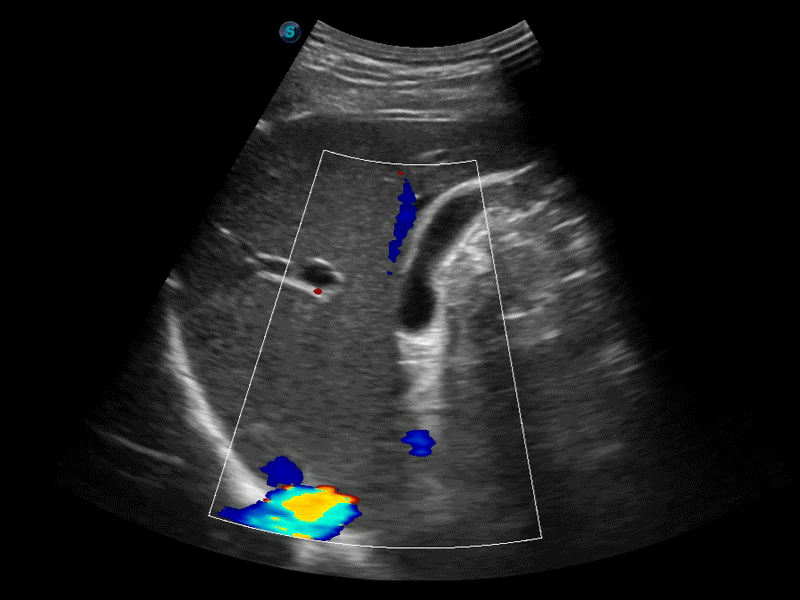

高分辨率血流成像技術(shù)提高了對(duì)低速血流信號(hào)的檢測(cè)能力。在提高空間分辨率的同時(shí),也克服了血流外溢現(xiàn)象,為用戶提供更加真實(shí)的血流動(dòng)力學(xué)信息。

凸陣、線陣和相控陣探頭進(jìn)行實(shí)時(shí)掃描時(shí),開啟擴(kuò)展成像模式,可以擴(kuò)展超聲圖像視野,以便更完整地查看大的病灶或組織器官的解剖結(jié)構(gòu)。

通過色彩血流和實(shí)時(shí)寬景相結(jié)合,可觀察到完整的靜脈或動(dòng)脈的血流,方便醫(yī)生檢查。實(shí)時(shí)掃查過程中,如有任何操作失誤也可以很容易地進(jìn)行回掃擦除,而不會(huì)中斷掃查。